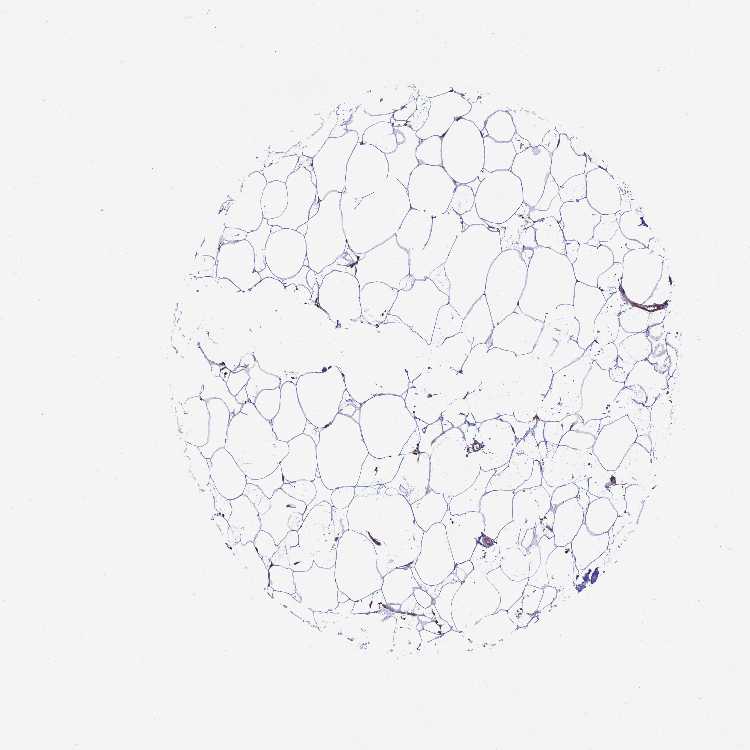

ADIPOSE TISSUE - Antibody stainingi

Antibody staining in the annotated cell types in the current human tissue is reported as not detected, low, medium, or high, based on conventional immunohistochemistry profiling in selected tissues. This score is based on the combination of the staining intensity and fraction of stained cells.

Each image is clickable and will lead to virtual microscopy that enables deeper exploration of all samples and also displays staining intensity scores, fraction scores and subcellular localization as well as patient and tissue information for each sample.

Antibody HPA043170

Adipocytes Not detected